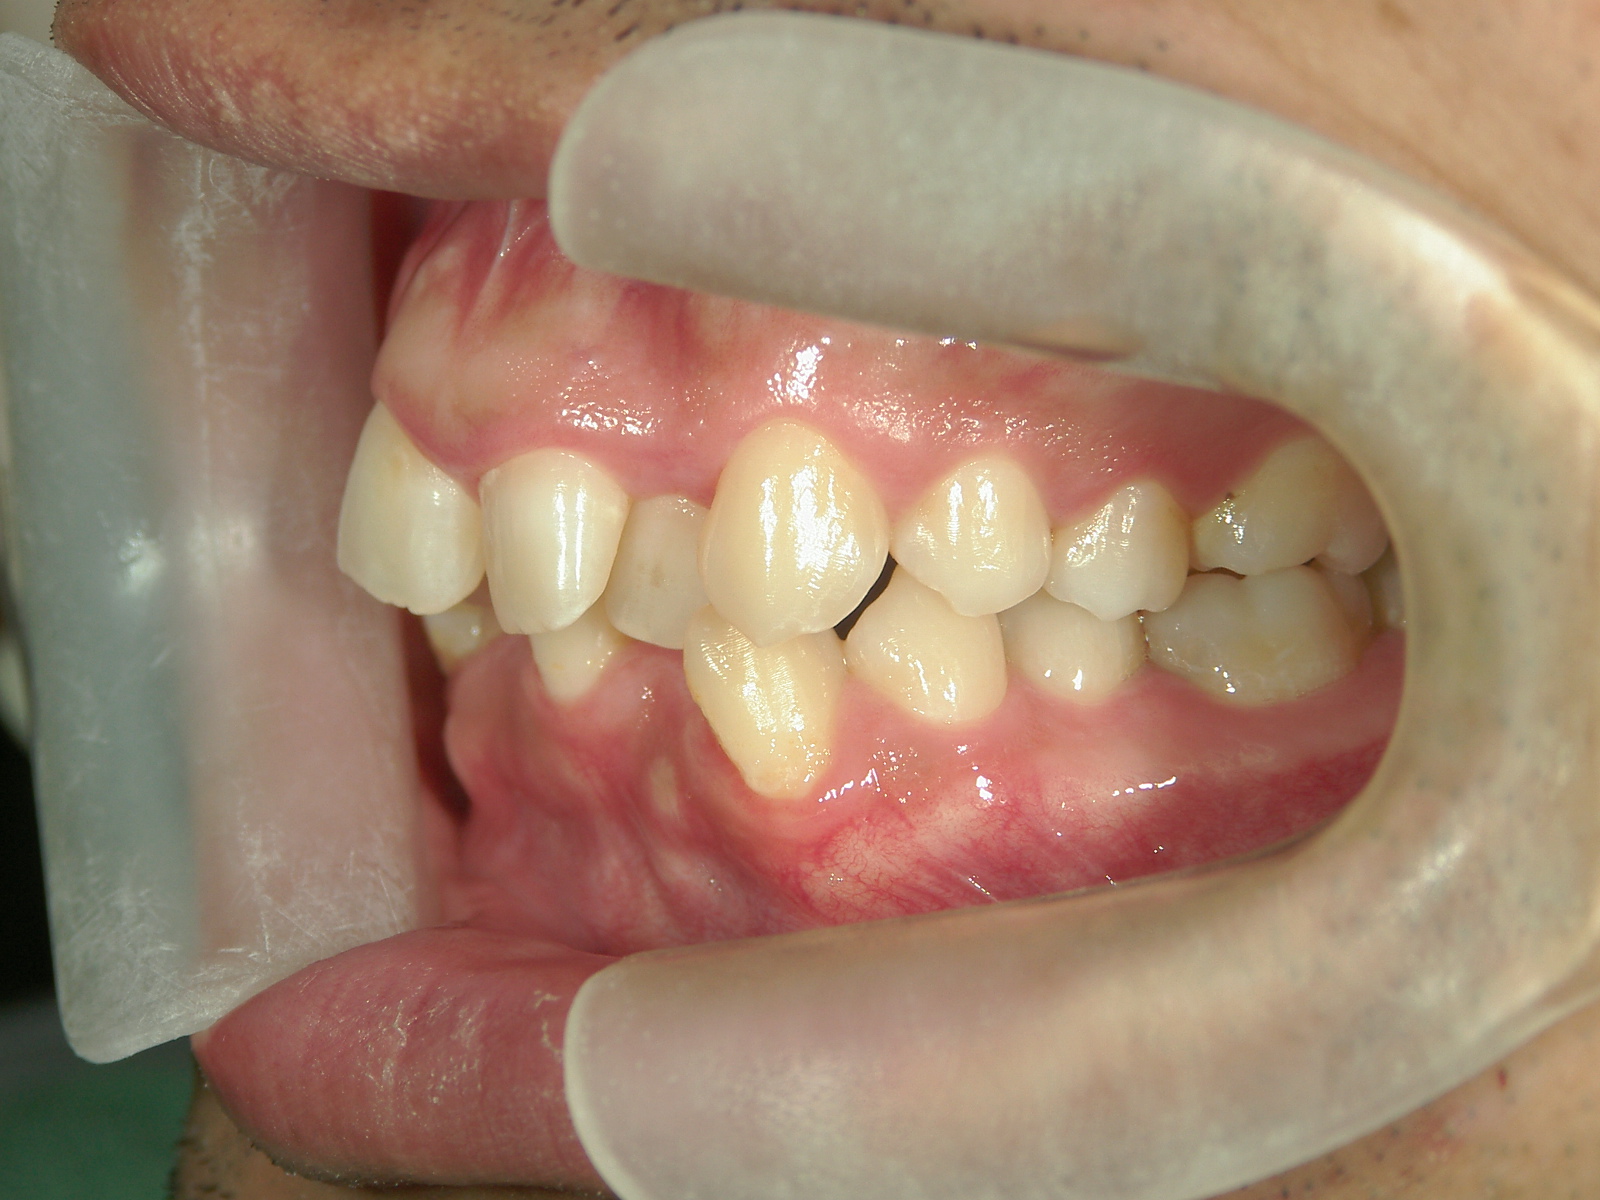

全顎ワイヤー矯正 症例(79)

主訴: 前歯が噛み合わない。歯並びが気になる。

カテゴリー : ガタガタ(叢生) , 噛み合わせが深い(過蓋咬合)